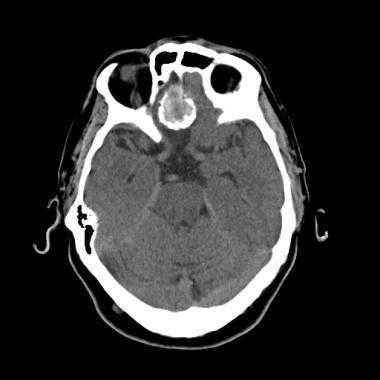

Псаммоматозная менингиома. КТ-исследование кальцифицированного объемного образования, обнаруженного на рентгеновском снимке. На томограмме, полученной на уровне верхней границы орбит, видна опухоль в области решетчатой пластинки (в области ольфакторной ямки).

Кальцинаты являются другой частой находкой; их обнаруживают в 20-25% случаев. Кальцинаты на КТ могут быть узловыми, точечными или сплошными плотными. Часто наблюдается вазогенный паренхиматозный отек окружающей мозговойо ткани, визуализирующийся на снимке как участок паренхимы пониженной плотности. В некоторых случаях отек настолько выражен, что, ввиду преимущественного поражения белого вещества, может выглядеть в виде пальцевидных зон низкой плотности. Впрочем, отек отсутствует примерно в 50% случаев вследствие медленного роста опухоли.

Компьютерная томография (КТ) часто используется для оценки опухолей мозга. Обычно на изображении без контрастного усиления она представлена в виде четко очерченного внемозгового (экстрааксиального) образования с ровными краями, прилегающего к твердой мозговой оболочке. Примерно 70-75% обладают повышенной плотностью по сравнению с окружающей их паренхимой головного мозга, а около 25% — изоденсивны. Редкая группа опухолей (липобластный подтип) содержат включения жира и, таким образом, характеризуются пониженной рентгеновской плотностью.